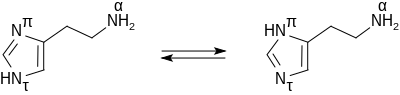

Histamine base, obtained as a mineral oil mull, melts at 83–84 °C.[8] Hydrochloride[9] and phosphorus[10] salts form white hygroscopic crystals and are easily dissolved in water or ethanol, but not in ether. In aqueous solution, the imidazole ring of histamine exists in two tautomeric forms, identified by which of the two nitrogen atoms is protonated. The nitrogen farther away from the side chain is the 'tele' nitrogen and is denoted by a lowercase tau sign and the nitrogen closer to the side chain is the 'pros' nitrogen and is denoted by the pi sign. The tele tautomer, Nτ-H-histamine, is preferred in solution as compared to the pros tautomer, Nπ-H-histamine.